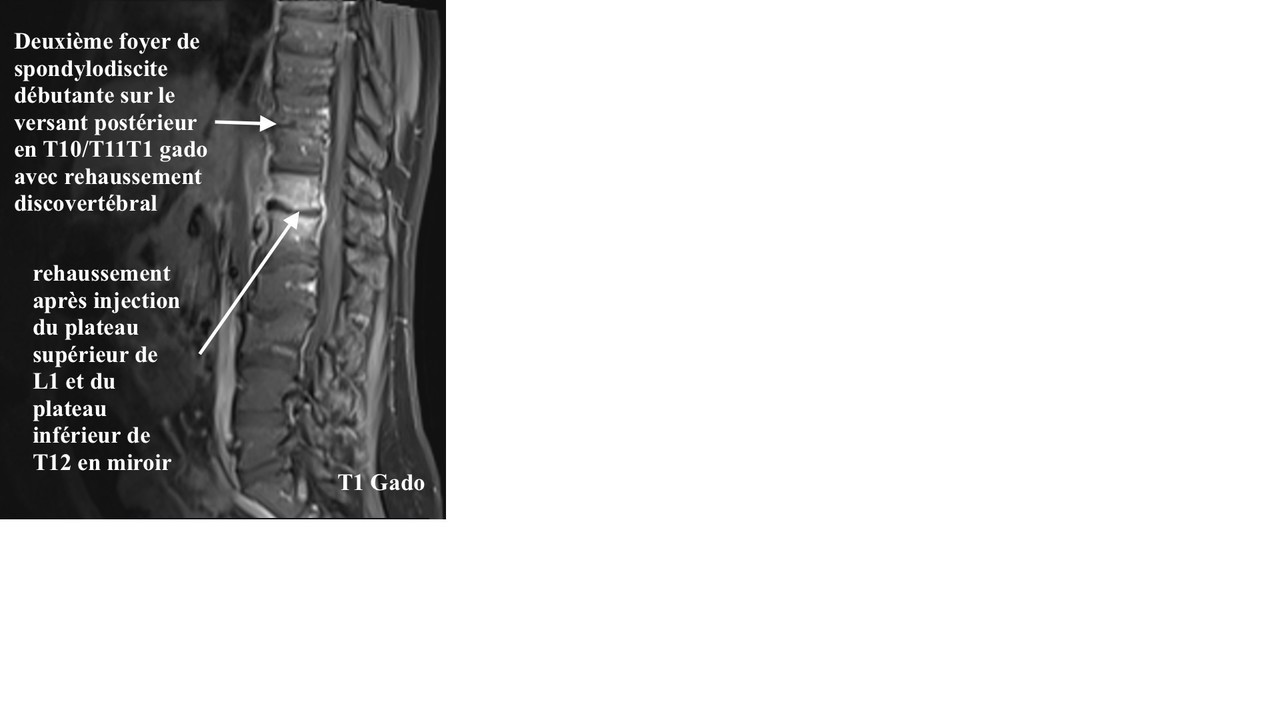

Une imagerie est réalisée, présentée ci-dessous (figure 4) :

Voici une séquence d’IRM séquence T2 STIR, puis T1 avec injection de gadolinium (figures 4 et 5).

L’IRM réalisée retrouve :

– épaississement des parties molles prérachidiennes en regard de T12/L1 ;

– présence d’un hypersignal STIR, hyposignal T1, se rehaussant après injection du plateau supérieur de L1 et du plateau inférieur de T12, en miroir associé à un abcès du muscle psoas gauche mesurant 10 x 11 mm dans un plan axial et près de 3 cm de hauteur ;

– présence d’une épidurite infectieuse millimétrique prédominant en région paramédiane et foraminale gauche venant au contact du sac dural et probable retentissement sur la racine T12 gauche dans sa portion foraminale ;

– absence d’anomalie formelle de signal du disque T12-L1 ;

– pas d’anomalie de signal visible du cône terminal et des racines de la queue de cheval ;

– deuxième foyer de spondylodiscite débutante sur le versant postérieur en T10/T11 avec rehaussement disco-vertébral, ainsi que spondylite très localisée du plateau inférieur de L3 ;

– pas de sténose foraminale ou anomalie discale significative visible aux étages sous-jacents (déformation sinueuse de l’espace intersomatique L2-L3 d’allure ancienne).